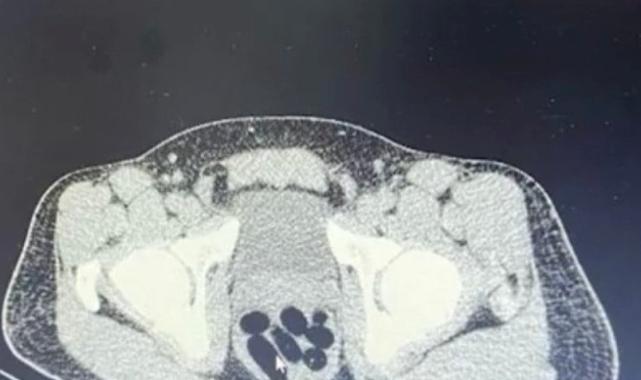

Gözaltına alınan şüphelinin hastanedeki iç beden muayenesinde 77 adet kapsül şeklinde 1 kilo 134 gram narkotik madde ele geçirildi.

Şüphelinin midesindeki maddeler cerrahi müdahale ile çıkarılırken hakkında uyuşturucu madde ticareti yapmak suçundan adli işlem başlatıldı.